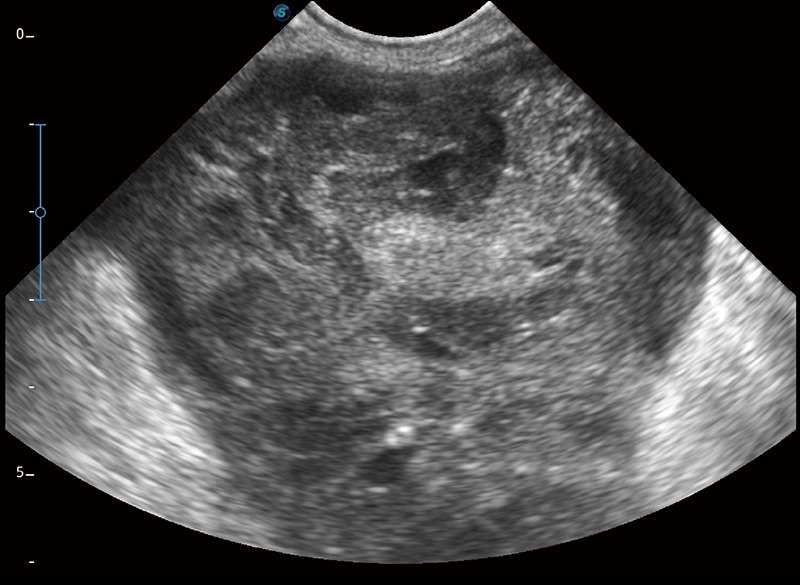

α1卓越的图像质量和便捷的工作流程,使每位宠物医生都能轻松扫查。其全面的兽用应用功能和紧凑型的结构设计,可以满足动物检查的多种需要。专业的预设检查模式和多领域测量软件包有助于为不同类型的动物提供检查, 让宠物医生能够出色的完成工作。

任意波束合成技术

在不牺牲时间分辨率的情况下提供出色的图像